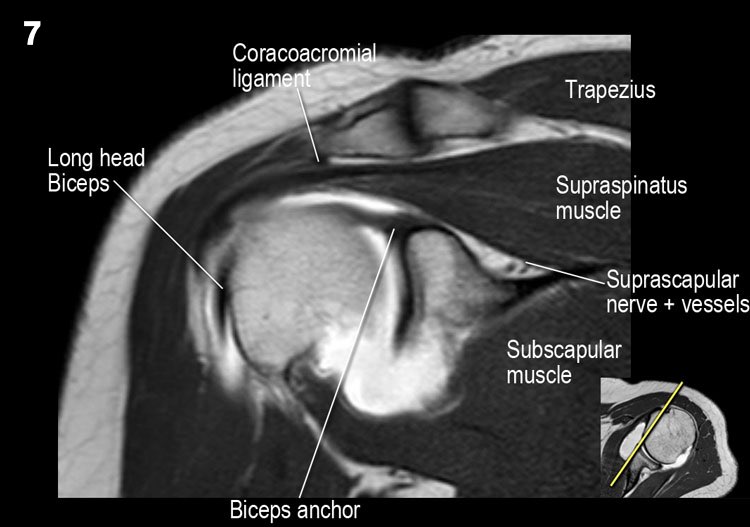

Giải phẫu mặt cắt vành và danh sách kiểm tra

- Lưu ý dây chằng quạ-đòn và đầu ngắn cơ nhị đầu.

- Lưu ý dây chằng quạ-mỏm cùng vai.

- Lưu ý thần kinh và mạch máu trên vai.

- Tìm kiếm hội chứng chèn ép cơ trên gai do gai xương khớp cùng-đòn hoặc dây chằng quạ-mỏm cùng vai dày lên.

- Đánh giá phức hợp sụn viền-gân cơ nhị đầu phần trên và tìm kiếm túi cùng dưới sụn viền hoặc rách SLAP.

- Tìm kiếm tràn dịch quá mức trong túi hoạt dịch dưới mỏm cùng vai và rách gân cơ trên gai.

- Tìm kiếm rách kiểu “rim-rent” của gân cơ trên gai tại chỗ bám của các thớ sợi trước.

- Đánh giá chỗ bám của dây chằng ổ chảo-cánh tay dưới (IGHL) vào xương cánh tay. Đánh giá phức hợp sụn viền-dây chằng phần dưới. Tìm kiếm tổn thương HAGL (bong điểm bám dây chằng ổ chảo-cánh tay tại xương cánh tay).

- Tìm kiếm rách gân cơ dưới gai.

- Lưu ý tổn thương Hill-Sachs nhỏ.

- Đánh giá điểm neo gân cơ nhị đầu.